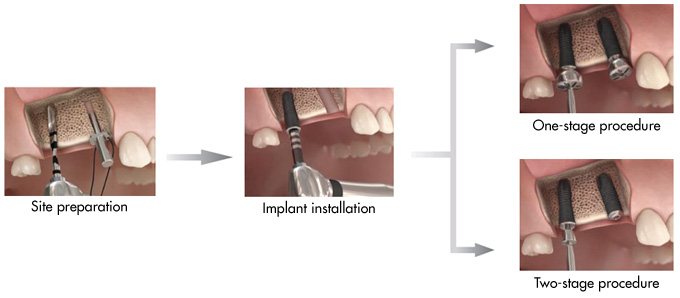

Function, beauty and biology in perfect harmony

The unique combination of independent features of the Astra Tech Implant System BioManagement Complex ensures a reliable, predictable and esthetic result both in the short and long term.